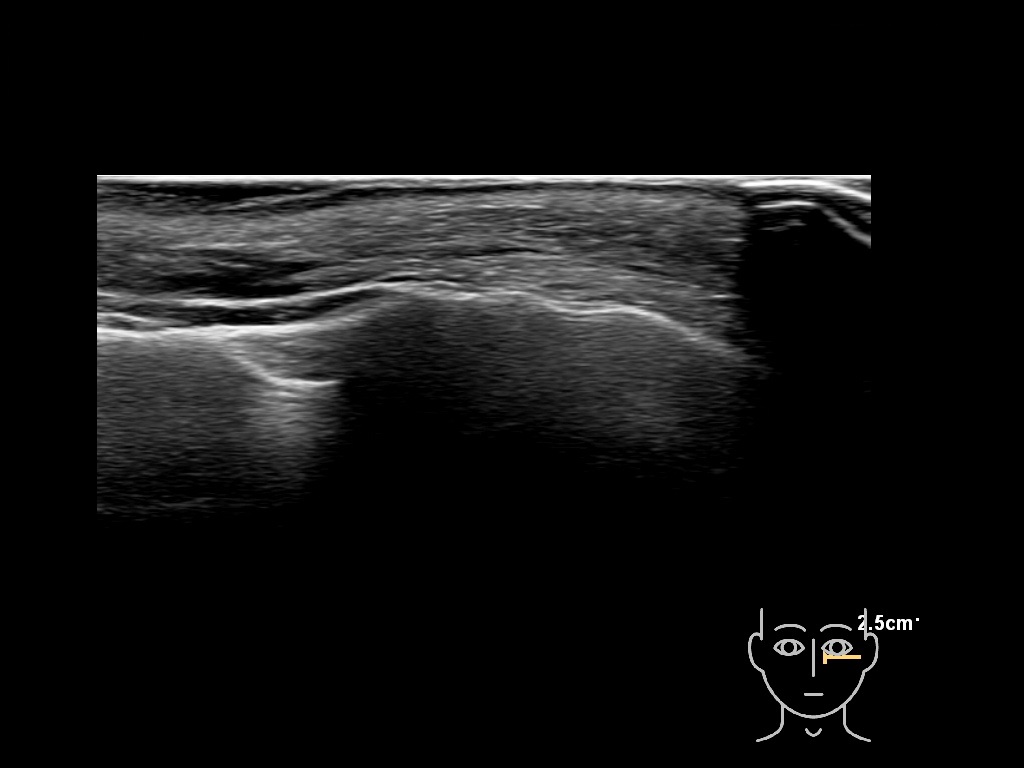

Study the first image to recognize the different layers. If you are sure about the layers, swipe to the second image to view the answer (if applicable).